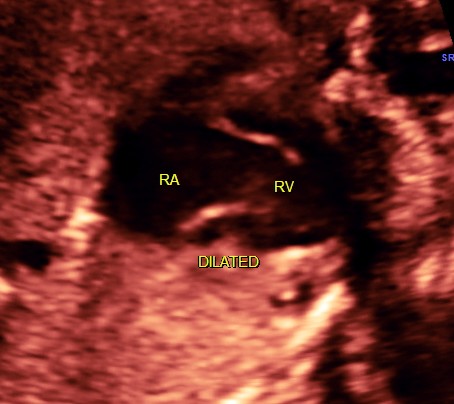

the following video shows right atrium and rt ventricle to be grossly dilated and the left atrium and left ventricle to be very small and hypoplastic.